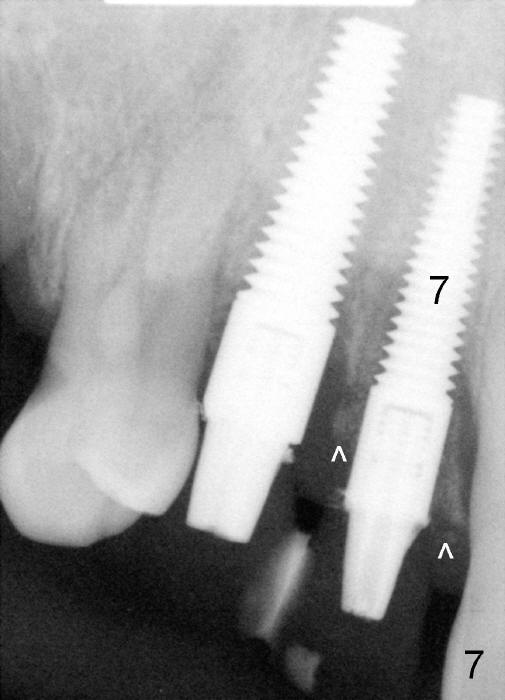

The most severely affected teeth (#6,7 and 9) are extracted and immediately replaced by 4x20 mm (#7) and 5x20 (#6,9) implants (Fig.4,5). Straight (0 degree) uniposts (3 and 4 mm, respectively) are rotated tightly into the wells of the implants by hand screw driver. In order to have reversibility to hybrid denture in the future, these uniposts are not cemented. Heavy retention grooves are placed between the uniposts and implants. Provisionals are fabricated immediately and cemented temporarily. To increase stability, flowable composite is added to the area between the provisionals of #6 and 7.

Dear Tony and Dr. Borgner: Thanks for the input. The patient showed up today. The provisional of #7 is off (Fig.9) and then recemented and bonded to the provisional of #6 with flowable composite. Open the magnified Fig.9 to see whether the vertical groove is wide and deep enough or not. By the way, the diameters of the implant and of the abutment are 4 and 3 mm, respectively.

The provisional of #9 is still wiggling a little bit buccolingually. It is probably due to loose connection between the implant and the abutment, although follow up PAs do not support it (Fig.7,8; ^: bone graft at the time of immediate implants).